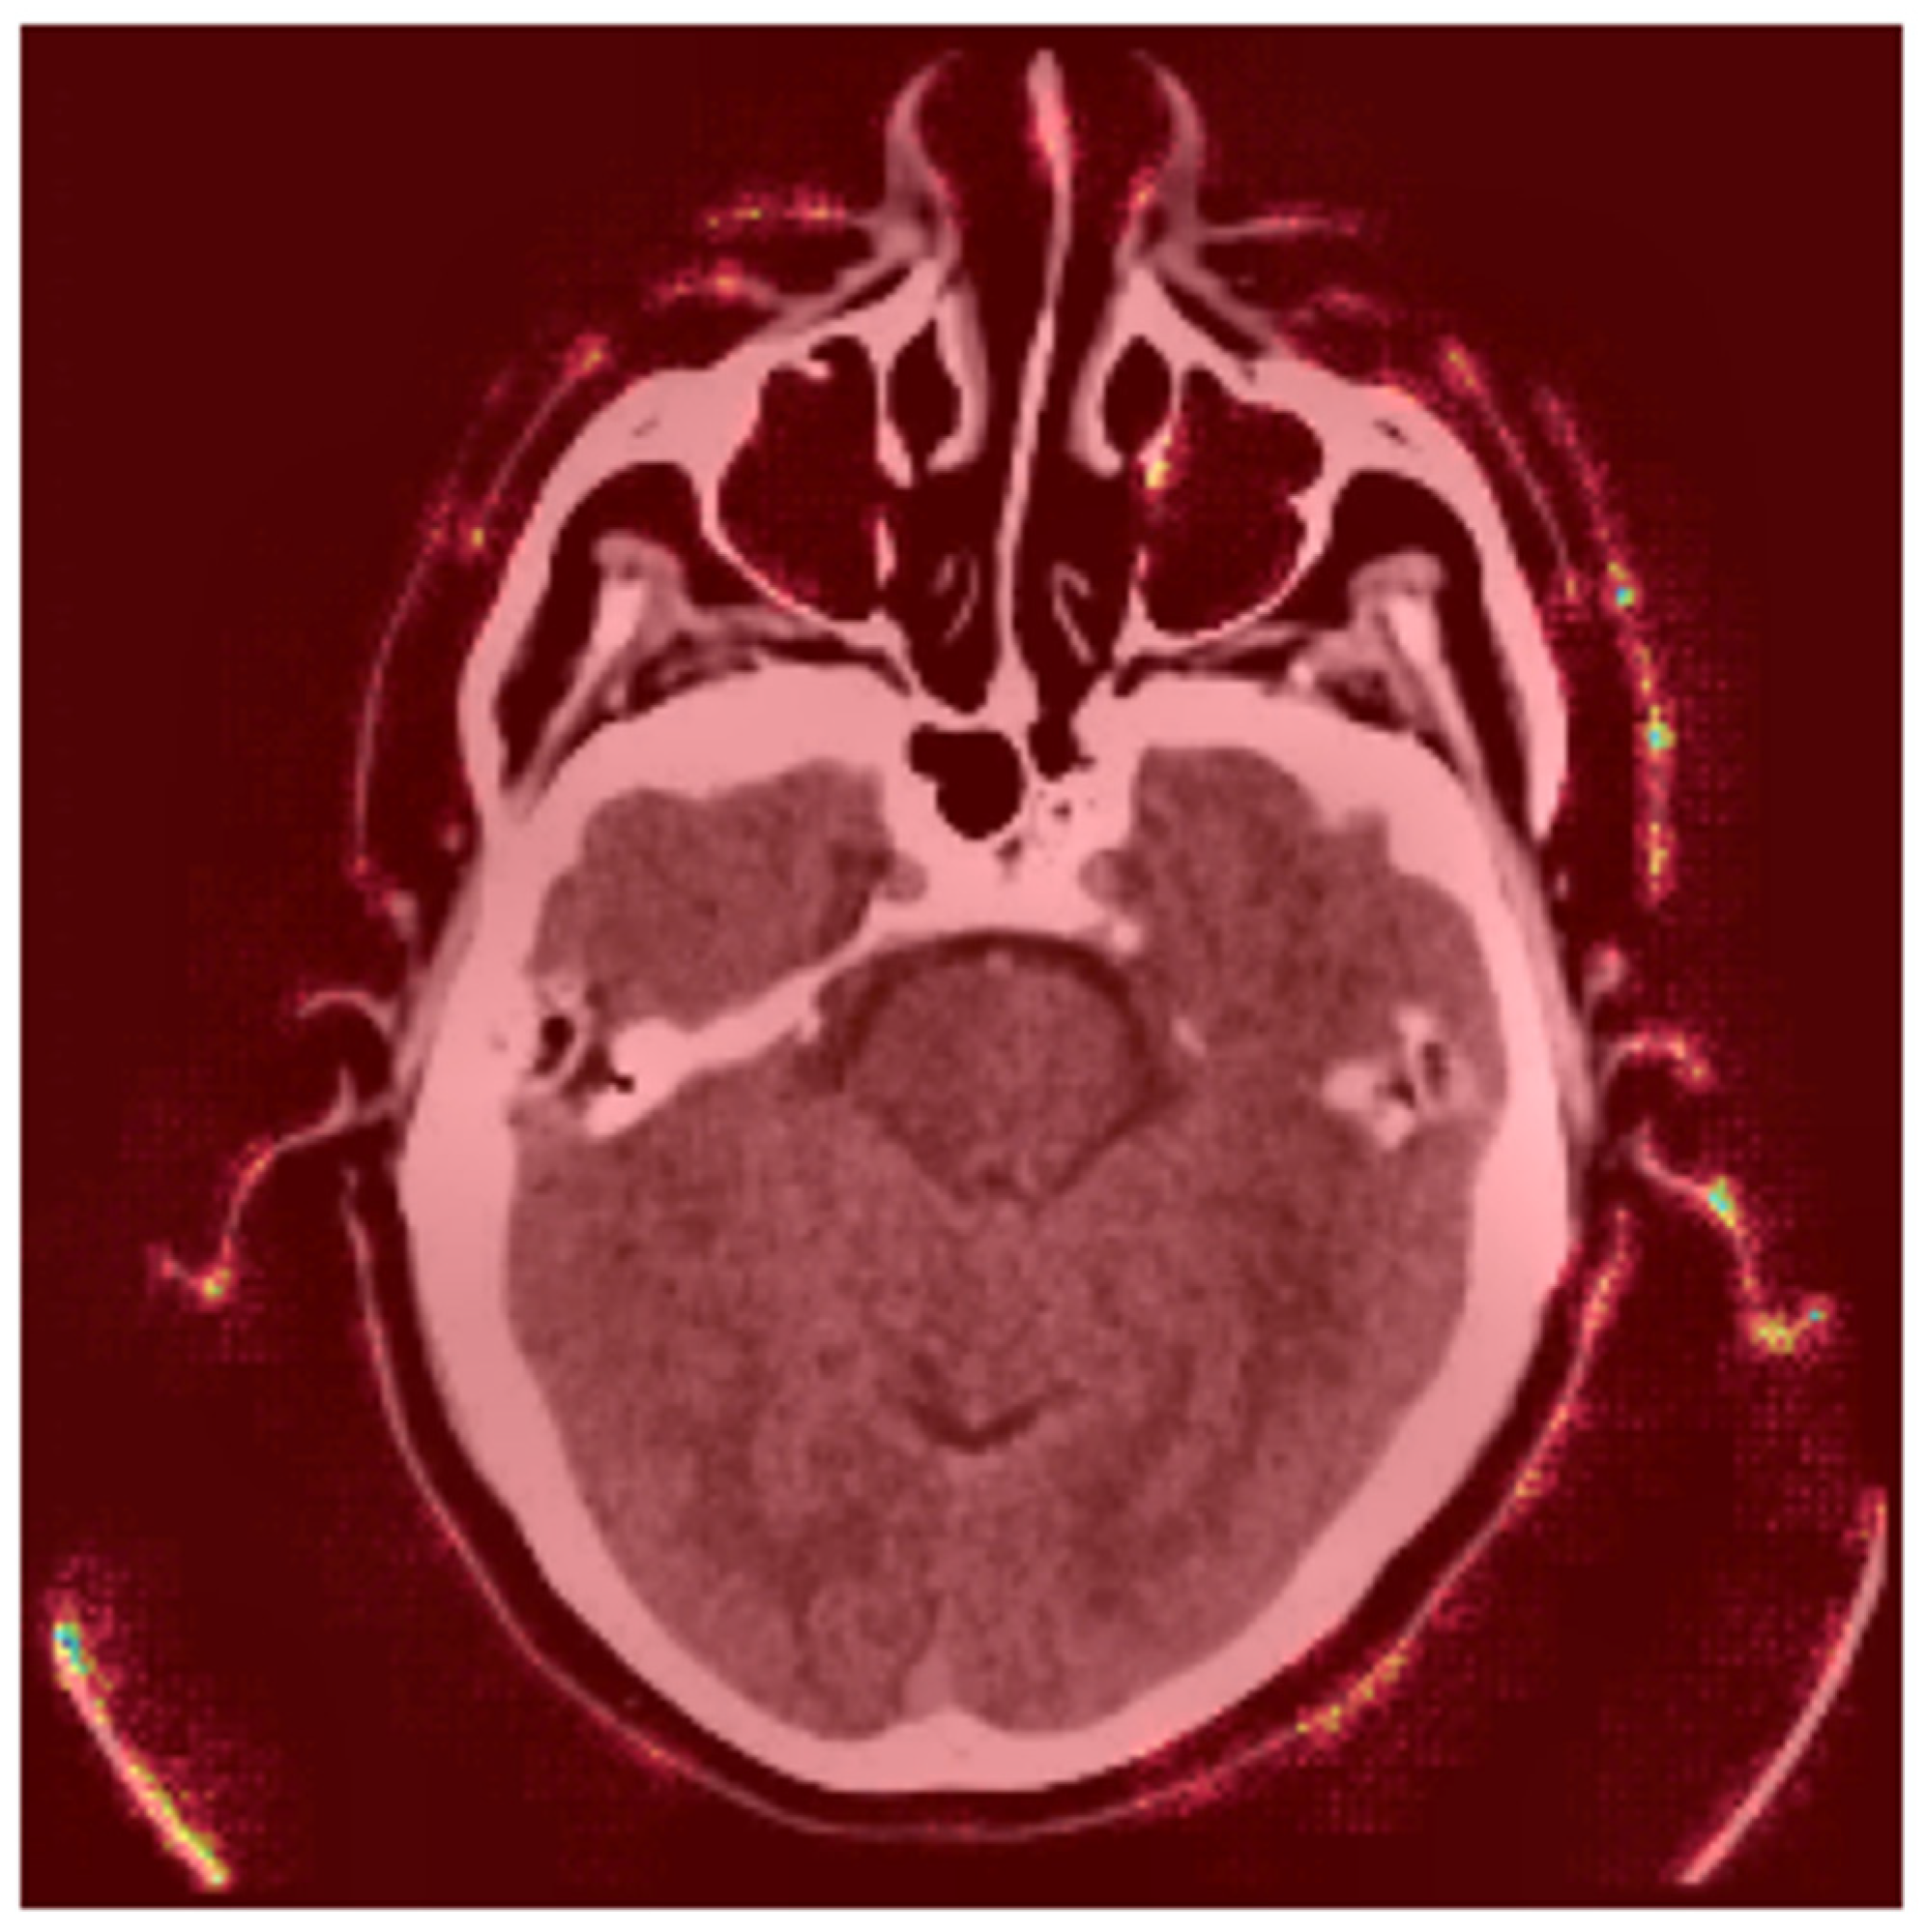

4.6.3. Gradient-Based Saliency Maps

- Red Areas: These regions, such as the hyperdense clot in the left hemisphere, are critical for the “Stroke” prediction. The model assigns high importance to these areas, aligning with clinical expectations that hyperdense regions indicate hemorrhagic strokes.

- Green/Blue Areas: These regions have minimal impact on the prediction, indicating that the model focuses on specific anatomical features rather than the entire image.

- Bright Spots (High Gradients): These regions correspond to areas where small changes in pixel values significantly alter the model’s output. For instance, the hyperdense clot (bright spots) is highlighted as a critical region for the “Stroke” prediction.

- Dark Regions (Low Gradients): These areas, such as the background or non-stroke-related anatomy, have little to no impact on the prediction, confirming the model’s focus on stroke-prone regions.